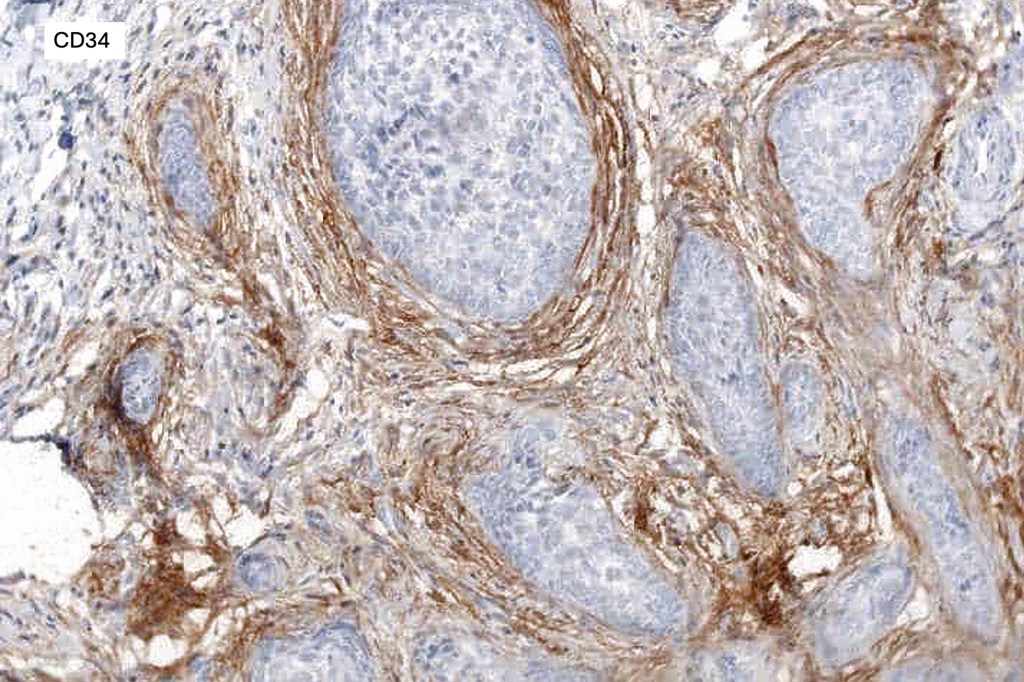

.Stromal CD10 & CD34